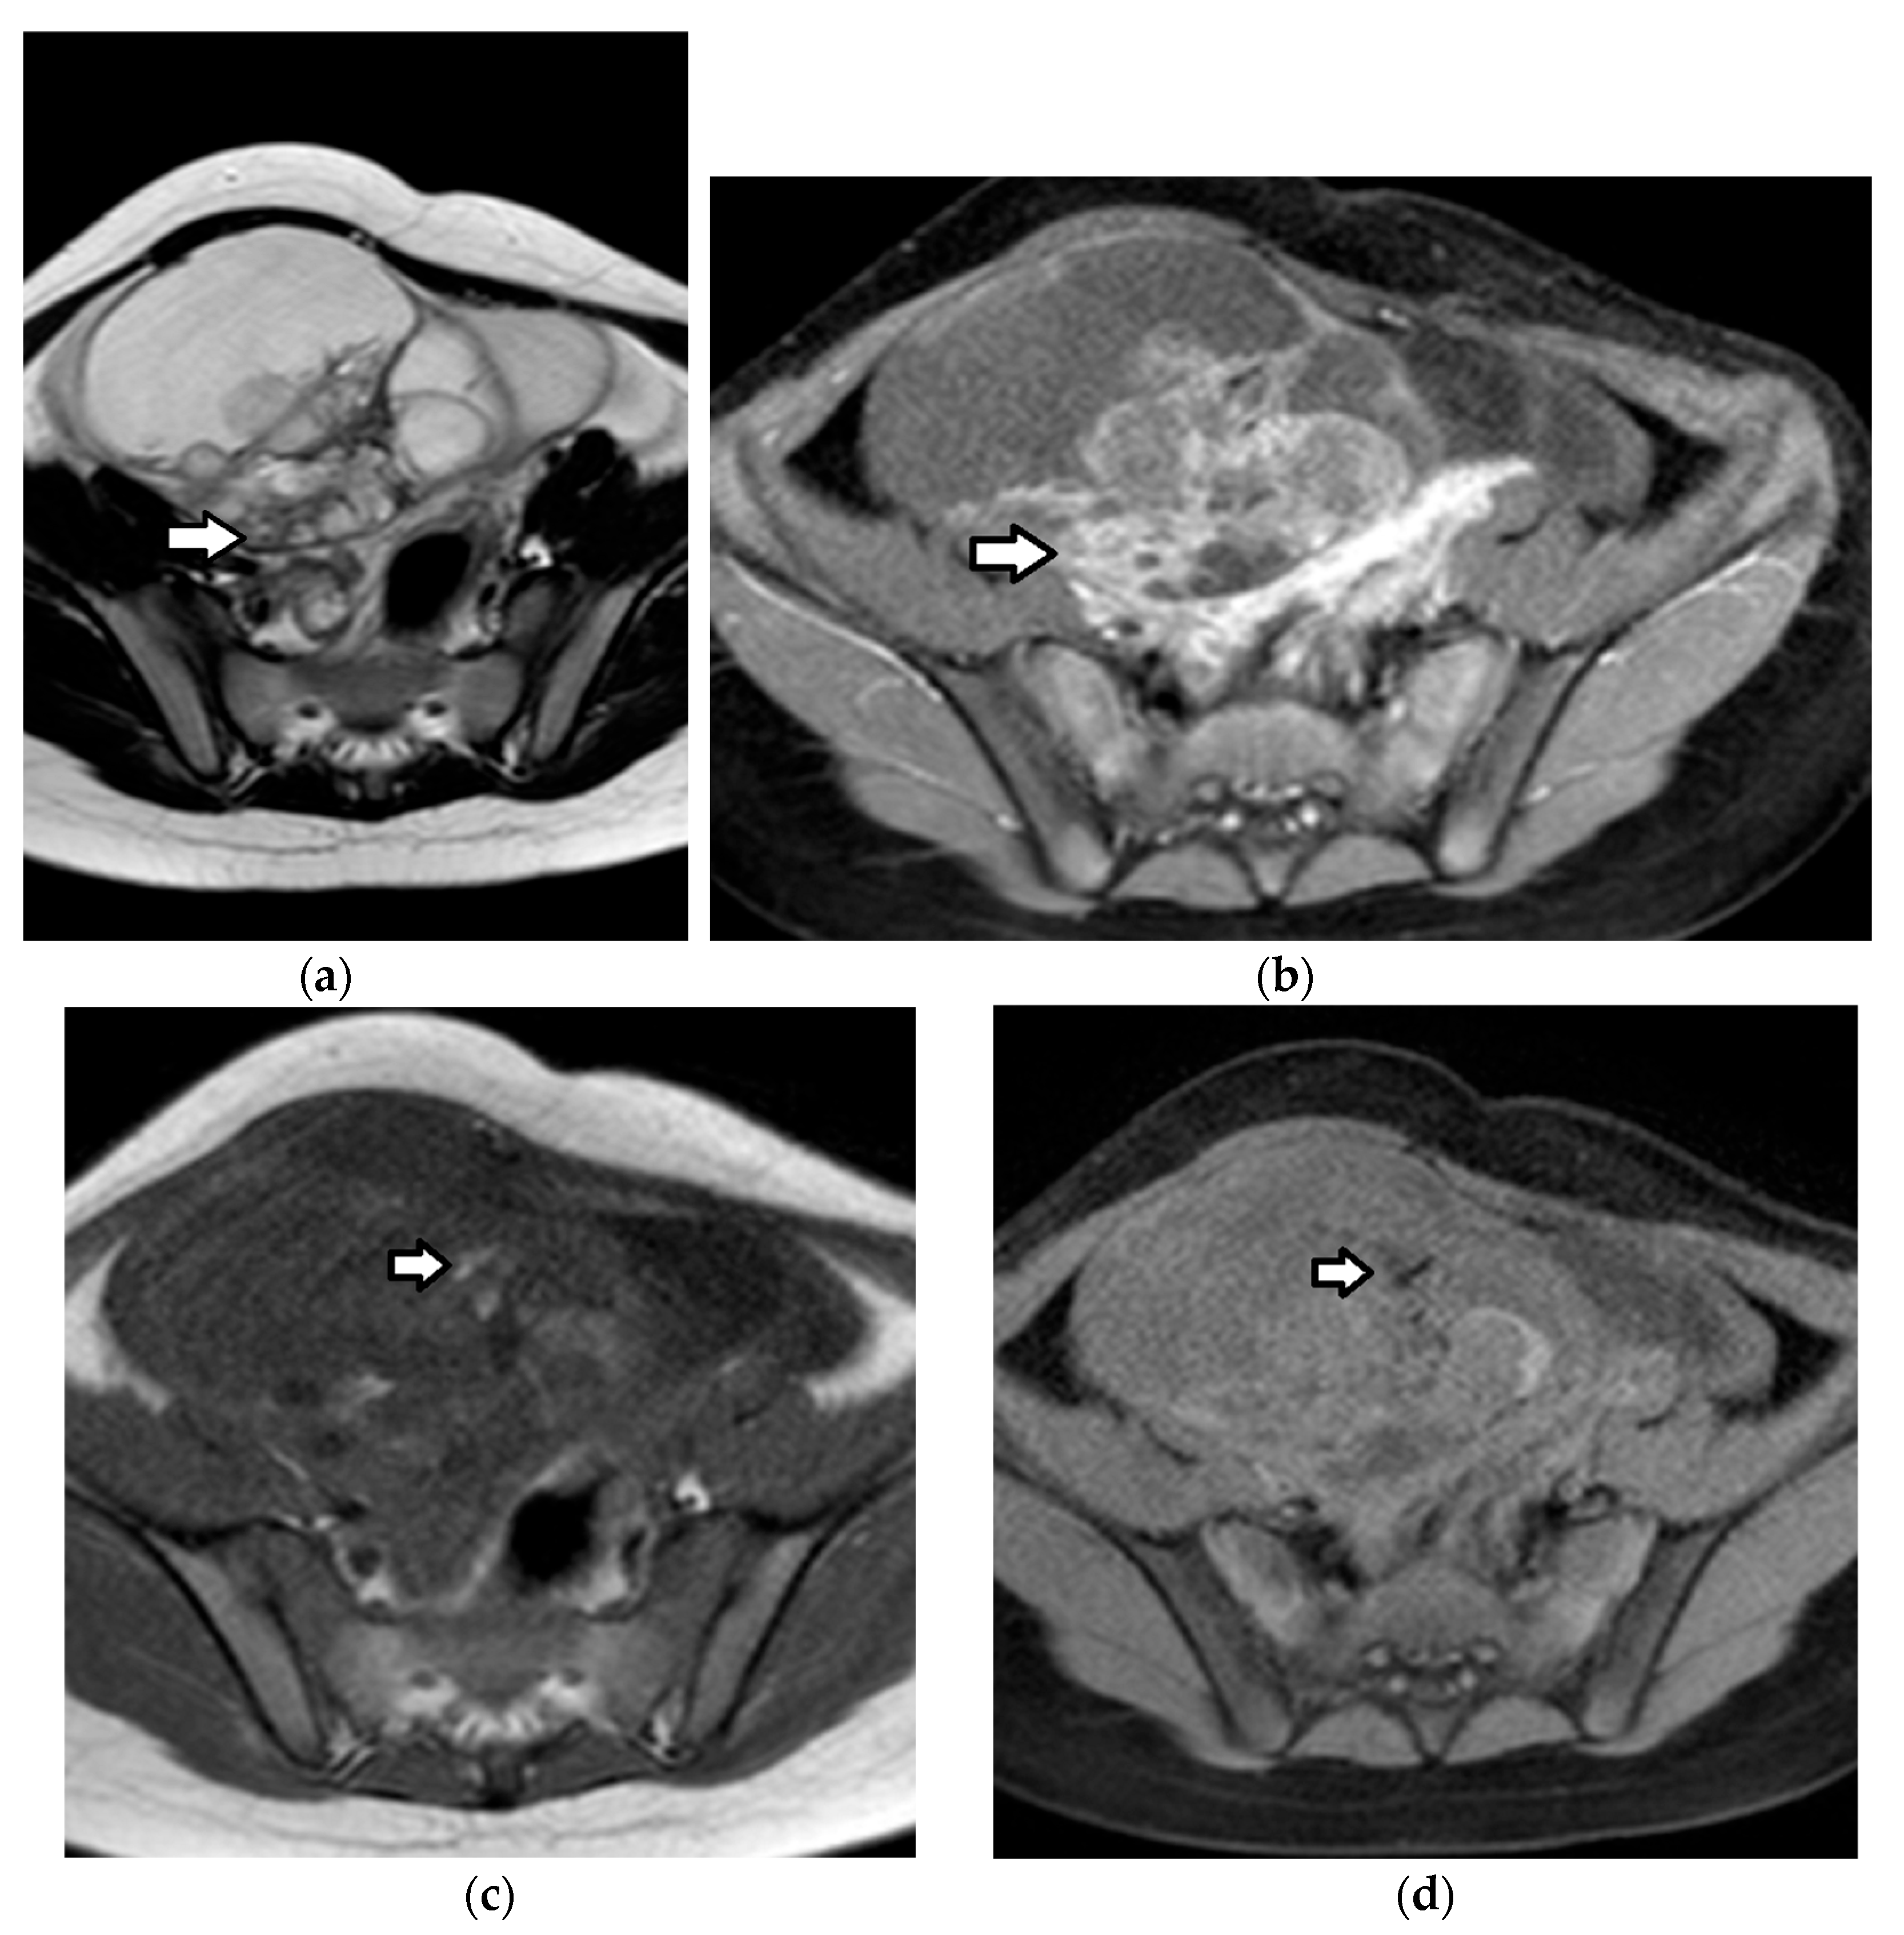

| Juvenile granulosa cell tumor | 75% of SCSTs mean age: 13 years bilateral: 4–5% secretes estrogens: signs of isosexual peripheral precocious puberty or menstrual irregularities secretes androgens: virilization (rarely) possible association with enchondromatosis syndromes: Maffuci syndrome, Ollier disease | malignant often diagnosed at an early stage excellent prognosis recurrence: rare | estrogens androgens (rarely) inhibin, especially inhibin B Müllerian Inhibiting Substance | nonspecific large size (mean diameter, 12.5 cm) multicystic tumor, with solid vascular components MRI

|